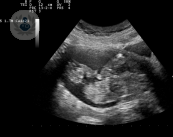

¿Qué relación hay entre la coagulación y la fertilidad?

En los últimos años, los tratamientos anticoagulantes y antiagregantes se han utilizado de manera prácticamente indiscriminada a la hora de manejar a este grupo de pacientes, pero cada vez son más los estudios que abogan por un tratamiento mucho más conservador.